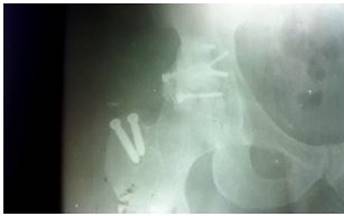

Dicha vía de abordaje es de elección en fracturas de la columna o pared posterior y con la realización de una osteotomía trocantérica se ofreció una amplia exposición de la zona afectada. Se realizó el abordaje posterior mencionado y la síntesis de las lesiones acetabulares mediante la combinación de tornillos y cerclaje, también fue preciso emplear cemento quirúrgico en una porción de la pared posterior para brindar mayor fortaleza a la osteosíntesis realizada.

Después se realizó rayos X. (Figura 3).